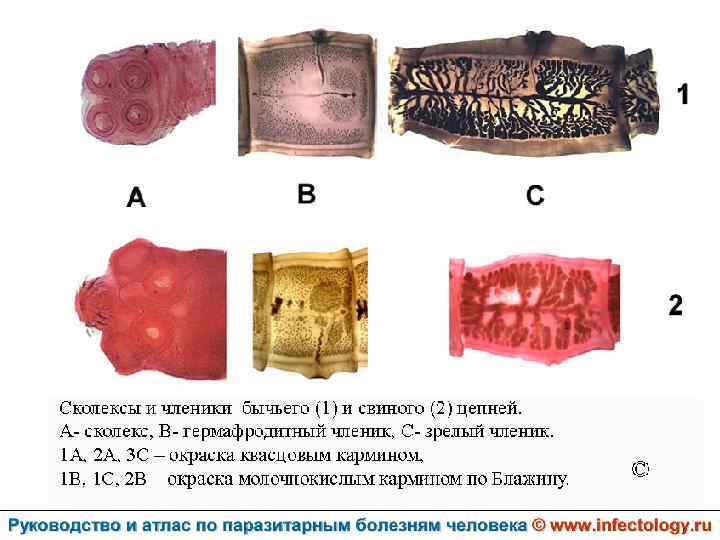

Тениаринхоз (шифр по МКБ 10 - B 68. 1) – антропонозный биогельминтоз с хроническим течением, характеризующийся преимущественно желудочно– кишечными расстройствами.

Тениоз (шифр по МКБ 10 - B 68. 0) – антропонозный биогельминтоз, одним из основных клинических проявлений которого является нарушение функций желудочно– кишечного тракта.